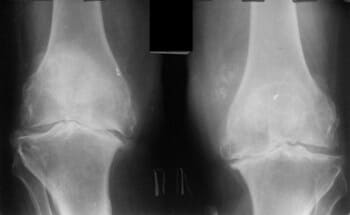

হাঁটু জয়েন্টের তরুণাস্থির উপর অস্টিওআর্থারাইটিসের প্রভাব।